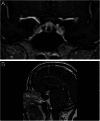

Results: Nine hundred and fifty-four patients received ICI therapy during the study period, and 37 (a prevalence of 3.9%) developed hypothalamic-pituitary-adrenal axis dysfunction. Their mean age was 65 years, and 70% were male. About 86.5% of the total patients affected were treated for metastatic malignancies. Ten of the 37 patients died during follow-up as a direct consequence or complication of their primary cancer diagnosis. The median interval for the onset of symptoms was 4 months. Following repeated testing, there was no recovery in cortisol or ACTH levels for any individual. Other permanent anterior pituitary hormone defects were unusual. Hypophysitis associated with immunotherapy appears to specifically target the corticotrophs, with no evidence of recovery over time. There was a specific abnormality seen in MRI scans of 7 of 27 patients who had scans, which appeared to be a particular feature of immune-mediated hypophysitis. These were confined to the anterior aspect of the pituitary gland, appearing as striations, and were not visible on any of the scans performed more than 3 months after the likely onset of the disease.

Conclusion: These data show that immune-related hypophysitis is a common complication of immune checkpoint inhibitor therapy. This may result in an imaging abnormality within the areas of the pituitary that are richest in corticotrophs. The endocrine consequence of this is a permanent defect in ACTH and, therefore, cortisol production.